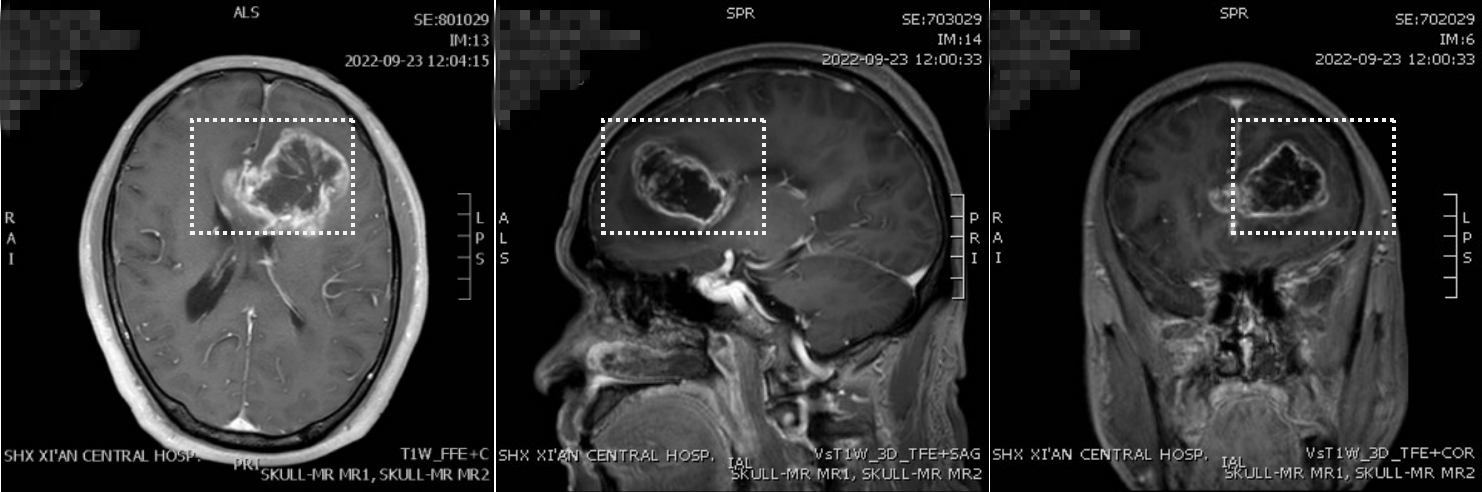

左侧额叶胶质母细胞瘤

胶质瘤起源于异常的或不可控制生长的脑细胞,而不是从身体其他部位转移而来的,被称为原发性脑胶质瘤。从肿瘤形态(表面上)和病理学(本质上)来看,可以分为低级别胶质瘤高级别胶质瘤。如果把良性肿瘤看作“好人”的话,那胶质瘤无疑是“坏人”。但是坏人也分不同程度的坏,比如低级别胶质瘤周围水肿较轻,对周围组织影响较小,属于“有点坏的坏人”,但高级别胶质瘤内有出血坏死,水肿重,对周围组织影响甚大,可以认为是“大坏人”